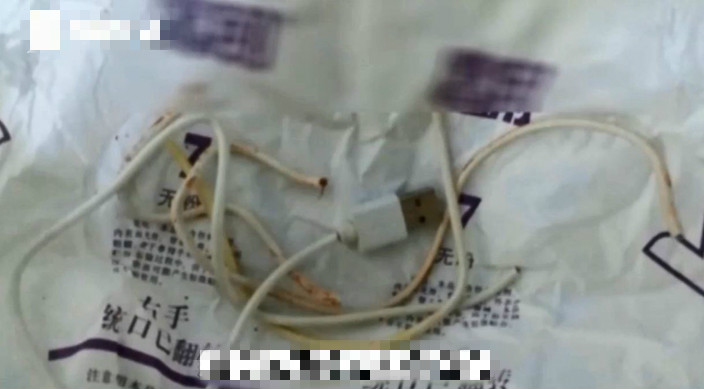

該名13歲的男童疑因對自己生殖器官感到好奇,因而剪掉USB線的插頭,然後塞入尿道,其後男童想自行取出,卻一直都拔不出來,更不敢告訴父母。直到他感到身體不適才告訴父母,其家人立即將他送到當地醫院治療,但即使醫生使用潤滑劑,亦無法將USB線拔出。

醫生為男童照X光,發現USB線已在其尿道進入了膀胱,而USB線更有超過20厘米長,更在膀胱打了死結,所以男童才無法自己取出。醫生表示,若強行將USB線拉出,會傷害尿道壁,而因為時間過長,男童的尿道已經受損。最終USB線在手術後已成功取出。